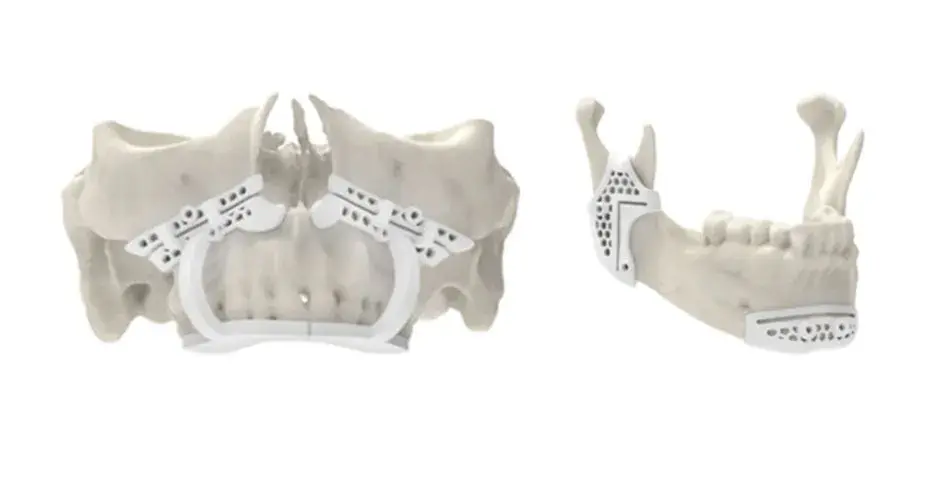

3D Systems' VSP® surgical planning solutions for craniomaxillofacial (CMF) applications received FDA clearance as a service-based approach to personalized surgery over 10 years ago.

3D Systems and Stryker Corporation have partnered to provide surgeons with best-in-class products and services for craniomaxillofacial surgeries. As a leader in personalized healthcare solutions, 3D Systems has planned and delivered devices for more than 140,000 patient-specific cases. The Stryker Craniomaxillofacial business specializes in providing patient-specific options and innovative solutions that help drive efficiencies in surgical suites. The combination of Stryker’s specialized team and advanced implants with 3D Systems' cutting-edge 3D printing technologies and expert consulting services positions both companies to provide a superior level of service to healthcare professionals who use these revolutionary solutions.